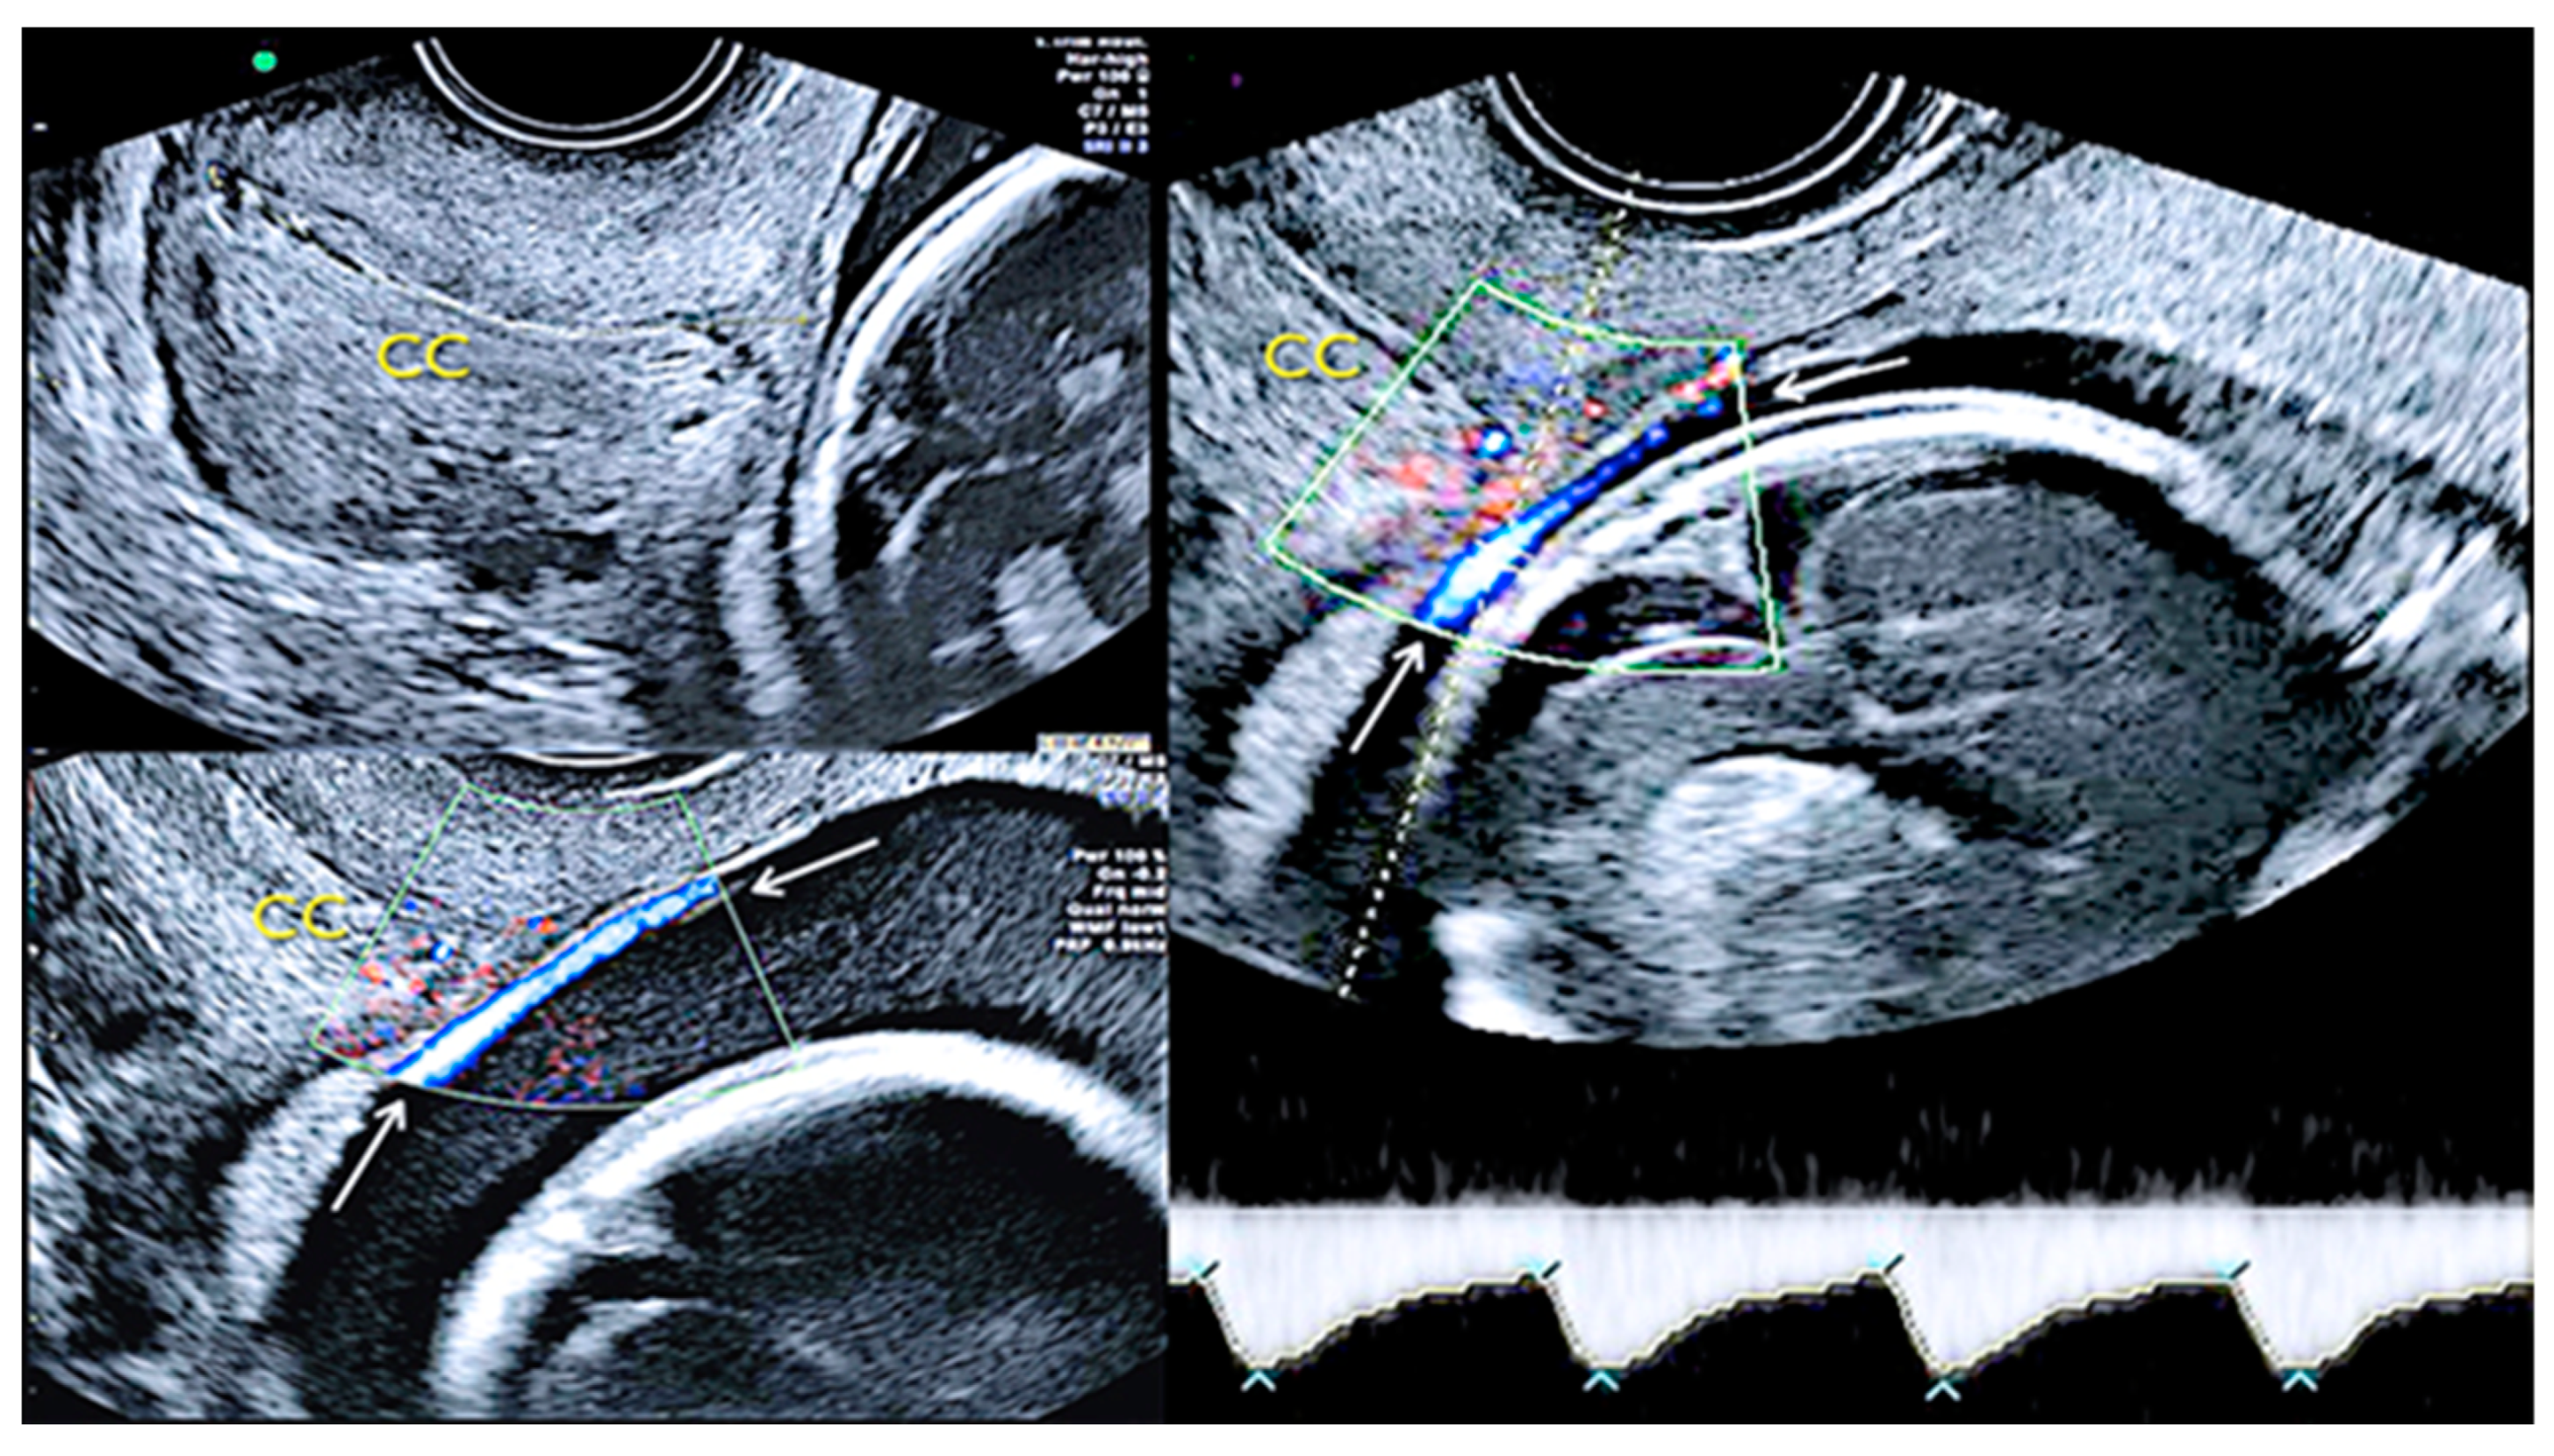

3.2.2. Vasa Praevia

3.2.3. Velamentous Umbilical Cord Insertion